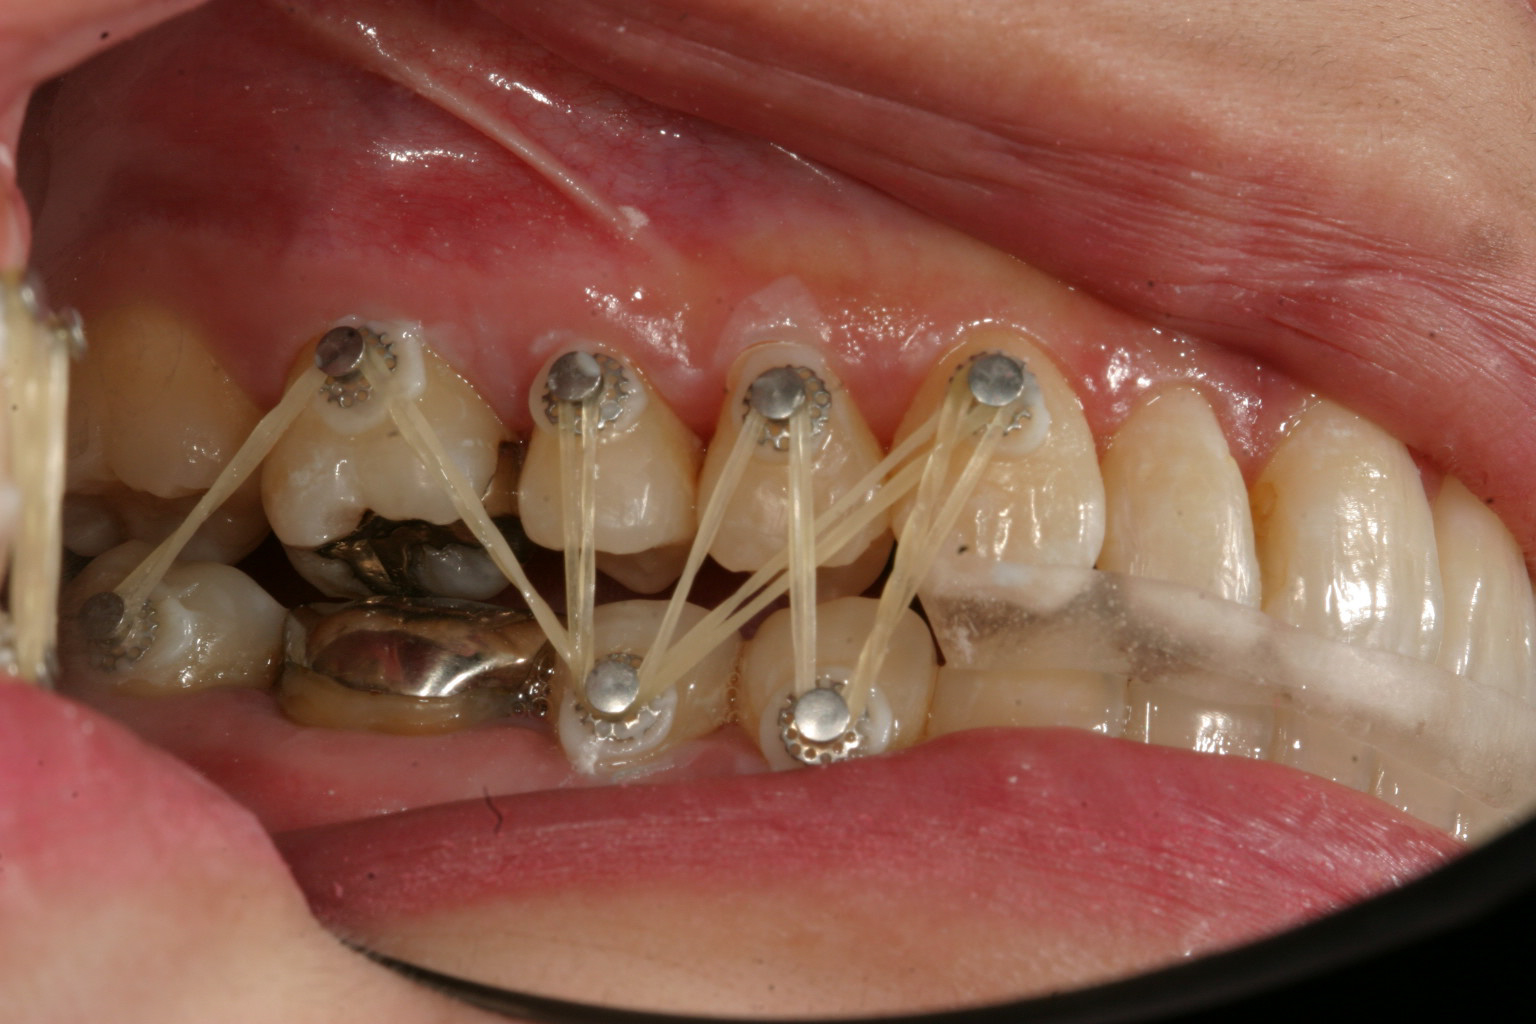

臼歯部離開の為前歯に自家製咬合閉鎖ジグを前歯に咬まして臼歯部にボタン付けてアップダウンエラスティック使用。